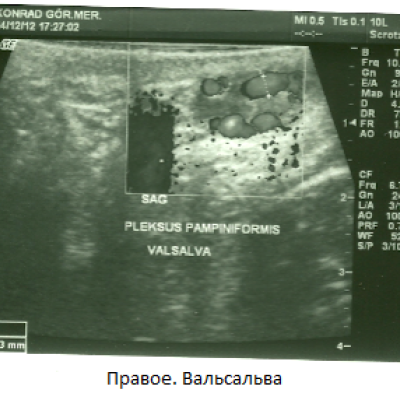

Мужу сделали УЗИ. Доктор сказал, что у мужа двустороннее варикоцеле. Нужна операция. Вот результаты УЗИ:

Чуть расширенные вены правого гроздевидного венозного сплетения и наблюдается извилистость. Максимальный диаметр вен в расслабленном состоянии 2.22 мм., при проведении пробы Вальсальве 2,73 мм. В положении лежа при проведении пробы Вальсальве количественное увеличение венозных структур, увеличение диаметра до патологического размера. В режиме ЦДК, при проведении пробы Вальсальве был выявлен кровоток в обратном направлении - рефлюкс .

Фото тоже я прикрепила